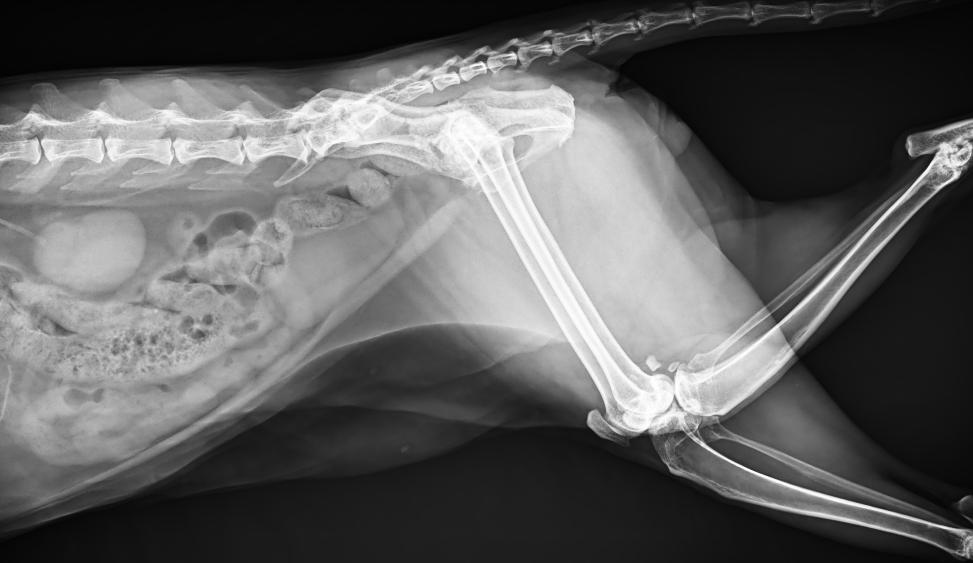

● 17*17大尺寸平板探測器,獲得高質(zhì)量圖像

● 優(yōu)異的空間分辨率及信噪比,提升圖像質(zhì)量

● 采用線(xiàn)噪聲消除技術(shù),使成像質(zhì)量提升40%

● 智能高效的圖像處理軟件,大幅提升圖像質(zhì)量